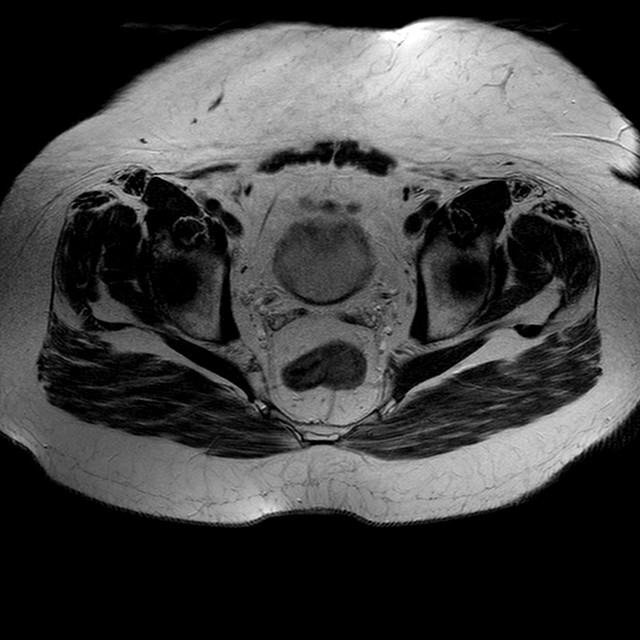

Esami: RMN BACINO

T2w TSE

Evidenti e simmetriche alterazioni osteofitosiche in regione coxo femorale con riduzione delle rime articolari. Degenerazione completa del cercine glenoideo. Non attuali segni di versamento articolare. Non segni di edema osseo che escludono attuale algodistrofia od osteonecrosi. Lieve e simmetrica riduzione del trofismo della muscolatura glutea.